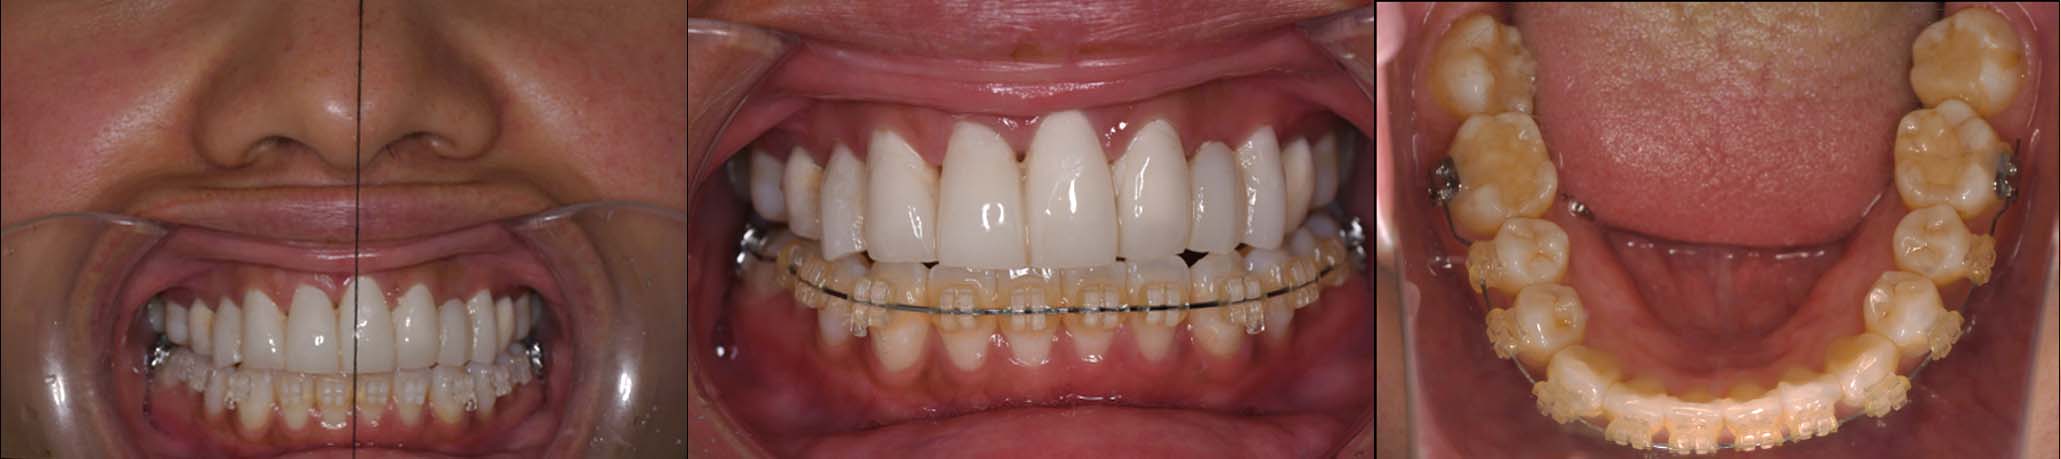

⑤2024年5月 上顎前歯部8本へ仮歯(TEK)

を装着

2024年 10月 下顎MTM開始

2024年 10月10日